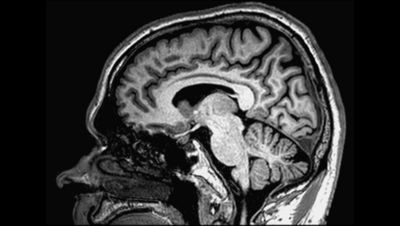

3d Brain Mri Images

A 3d Brain Surface Reconstruction From 3t Structural Mri Scan Of

3d T2 Brain Mri Imaging Youtube